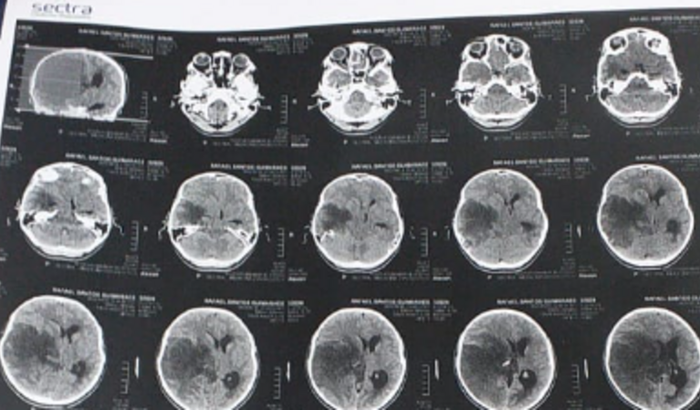

criei essa vaquinha no intuito de arrecadar dinheiro para o tratamento do meu sobrinho. ele se chama Rafael tem 14 anos e está com câncer no cérebro. Ele precisa fazer uma cirurgia de emergência em são Paulo. precisamos arrecadar R$10000,00 (dez mil reais)